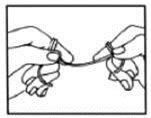

- You also need to clean around your teeth with dental floss every day. Careful flossing will take off plaque and leftover food that a toothbrush can’t reach. Be sure to rinse after you floss.

How to Floss

upper teeth.

See your dentist if brushing or flossing causes your gums to bleed or hurts your mouth. If you have trouble flossing, a floss holder may help. Ask your dentist to show you the right way to floss.